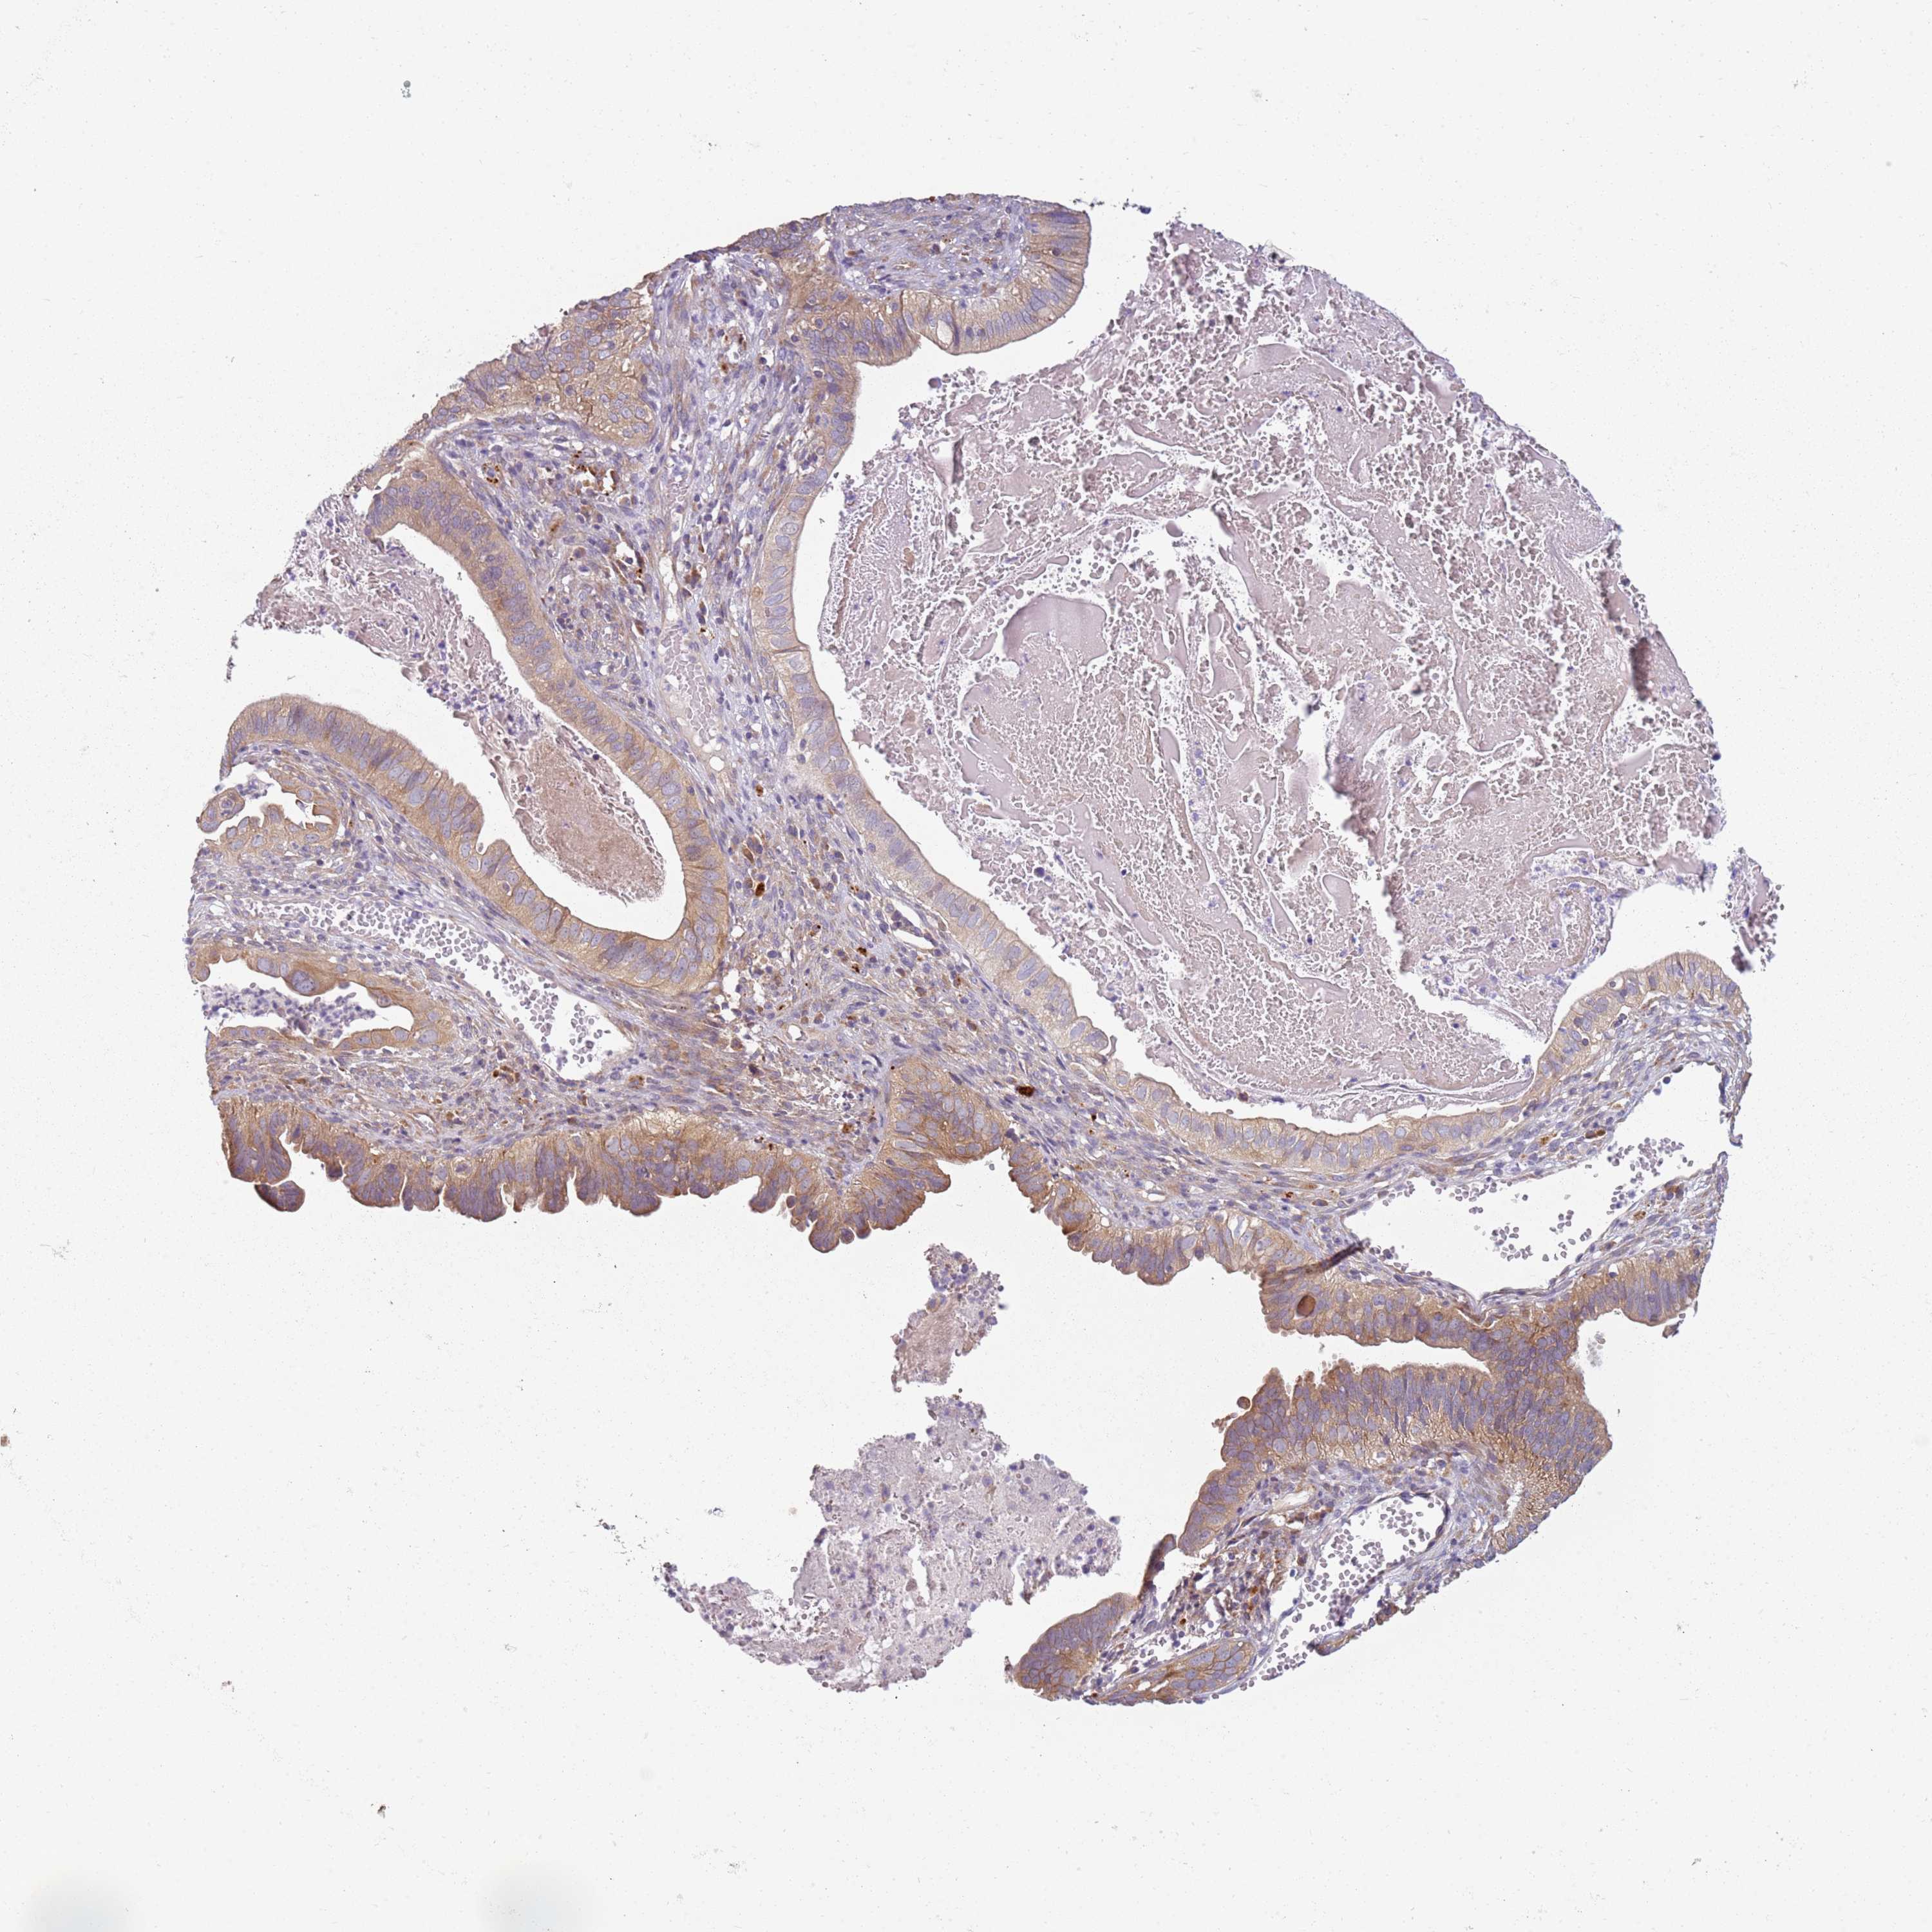

CERVICAL CANCER - Protein expressioni

A mouse-over function shows sample information and annotation data. Click on an image to view it in a full screen mode. Samples can be filtered based on level of antibody staining by selecting one or several of the following categories: high, medium, low and not detected. The assay and annotation is described here.

Note that samples used for immunohistochemistry by the Human Protein Atlas do not correspond to samples in the TCGA dataset.

Antibody stainingi

Antibody staining in the annotated cell types in the current human tissue is reported as not detected, low, medium, or high, based on conventional immunohistochemistry profiling in selected tissues. This score is based on the combination of the staining intensity and fraction of stained cells.

Each image is clickable and will lead to virtual microscopy that enables deeper exploration of all samples and also displays staining intensity scores, fraction scores and subcellular localization as well as patient and tissue information for each sample.

Antibody HPA047132

Staining

High

Medium

Low

Not detected

Intensity

Strong

Moderate

Weak

Negative

Quantity

>75%

75%-25%

<25%

None

Location

Nuclear

Cytoplasmic/membranous

Cytoplasmic/membranous,nuclear

Squamous cell carcinoma, NOS

Adenocarcinoma, NOS